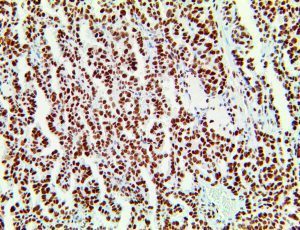

It is the ICU physician who is most likely to witness one of the deadliest manifestations of the abnormal immunological response, the cytokine storm syndrome (CSS). This response is also referred to by some as the cytokine release syndrome (CRS). CSS is characterized by continuous activation and expansion of macrophage and lymphocyte populations, which secrete large amounts of cytokines, causing the cytokine storm. This massive cytokine release is akin to hemophagocytic lymphohistiocytosis (HLH) disease, a syndrome characterized by initial unchecked and persistent activation of cytotoxic T lymphocytes and NK cells.

Clinical and laboratory manifestations of HLH include fever, enlarged liver and/or spleen, neurologic dysfunction, coagulopathy, liver dysfunction, cytopenias (i.e., low levels of erythrocytes, leukocytes, and/or platelets), hypertriglyceridemia, hyperferritinemia, hemophagocytosis, and eventually diminished NK cell activity as the immune system becomes progressively paralyzed. HLH can be familial (primary HLH) or secondary to another disease process (sHLH), such as rheumatic disease, in which it is referred to as macrophage activation syndrome (MAS, characterized by elevated ferritin).